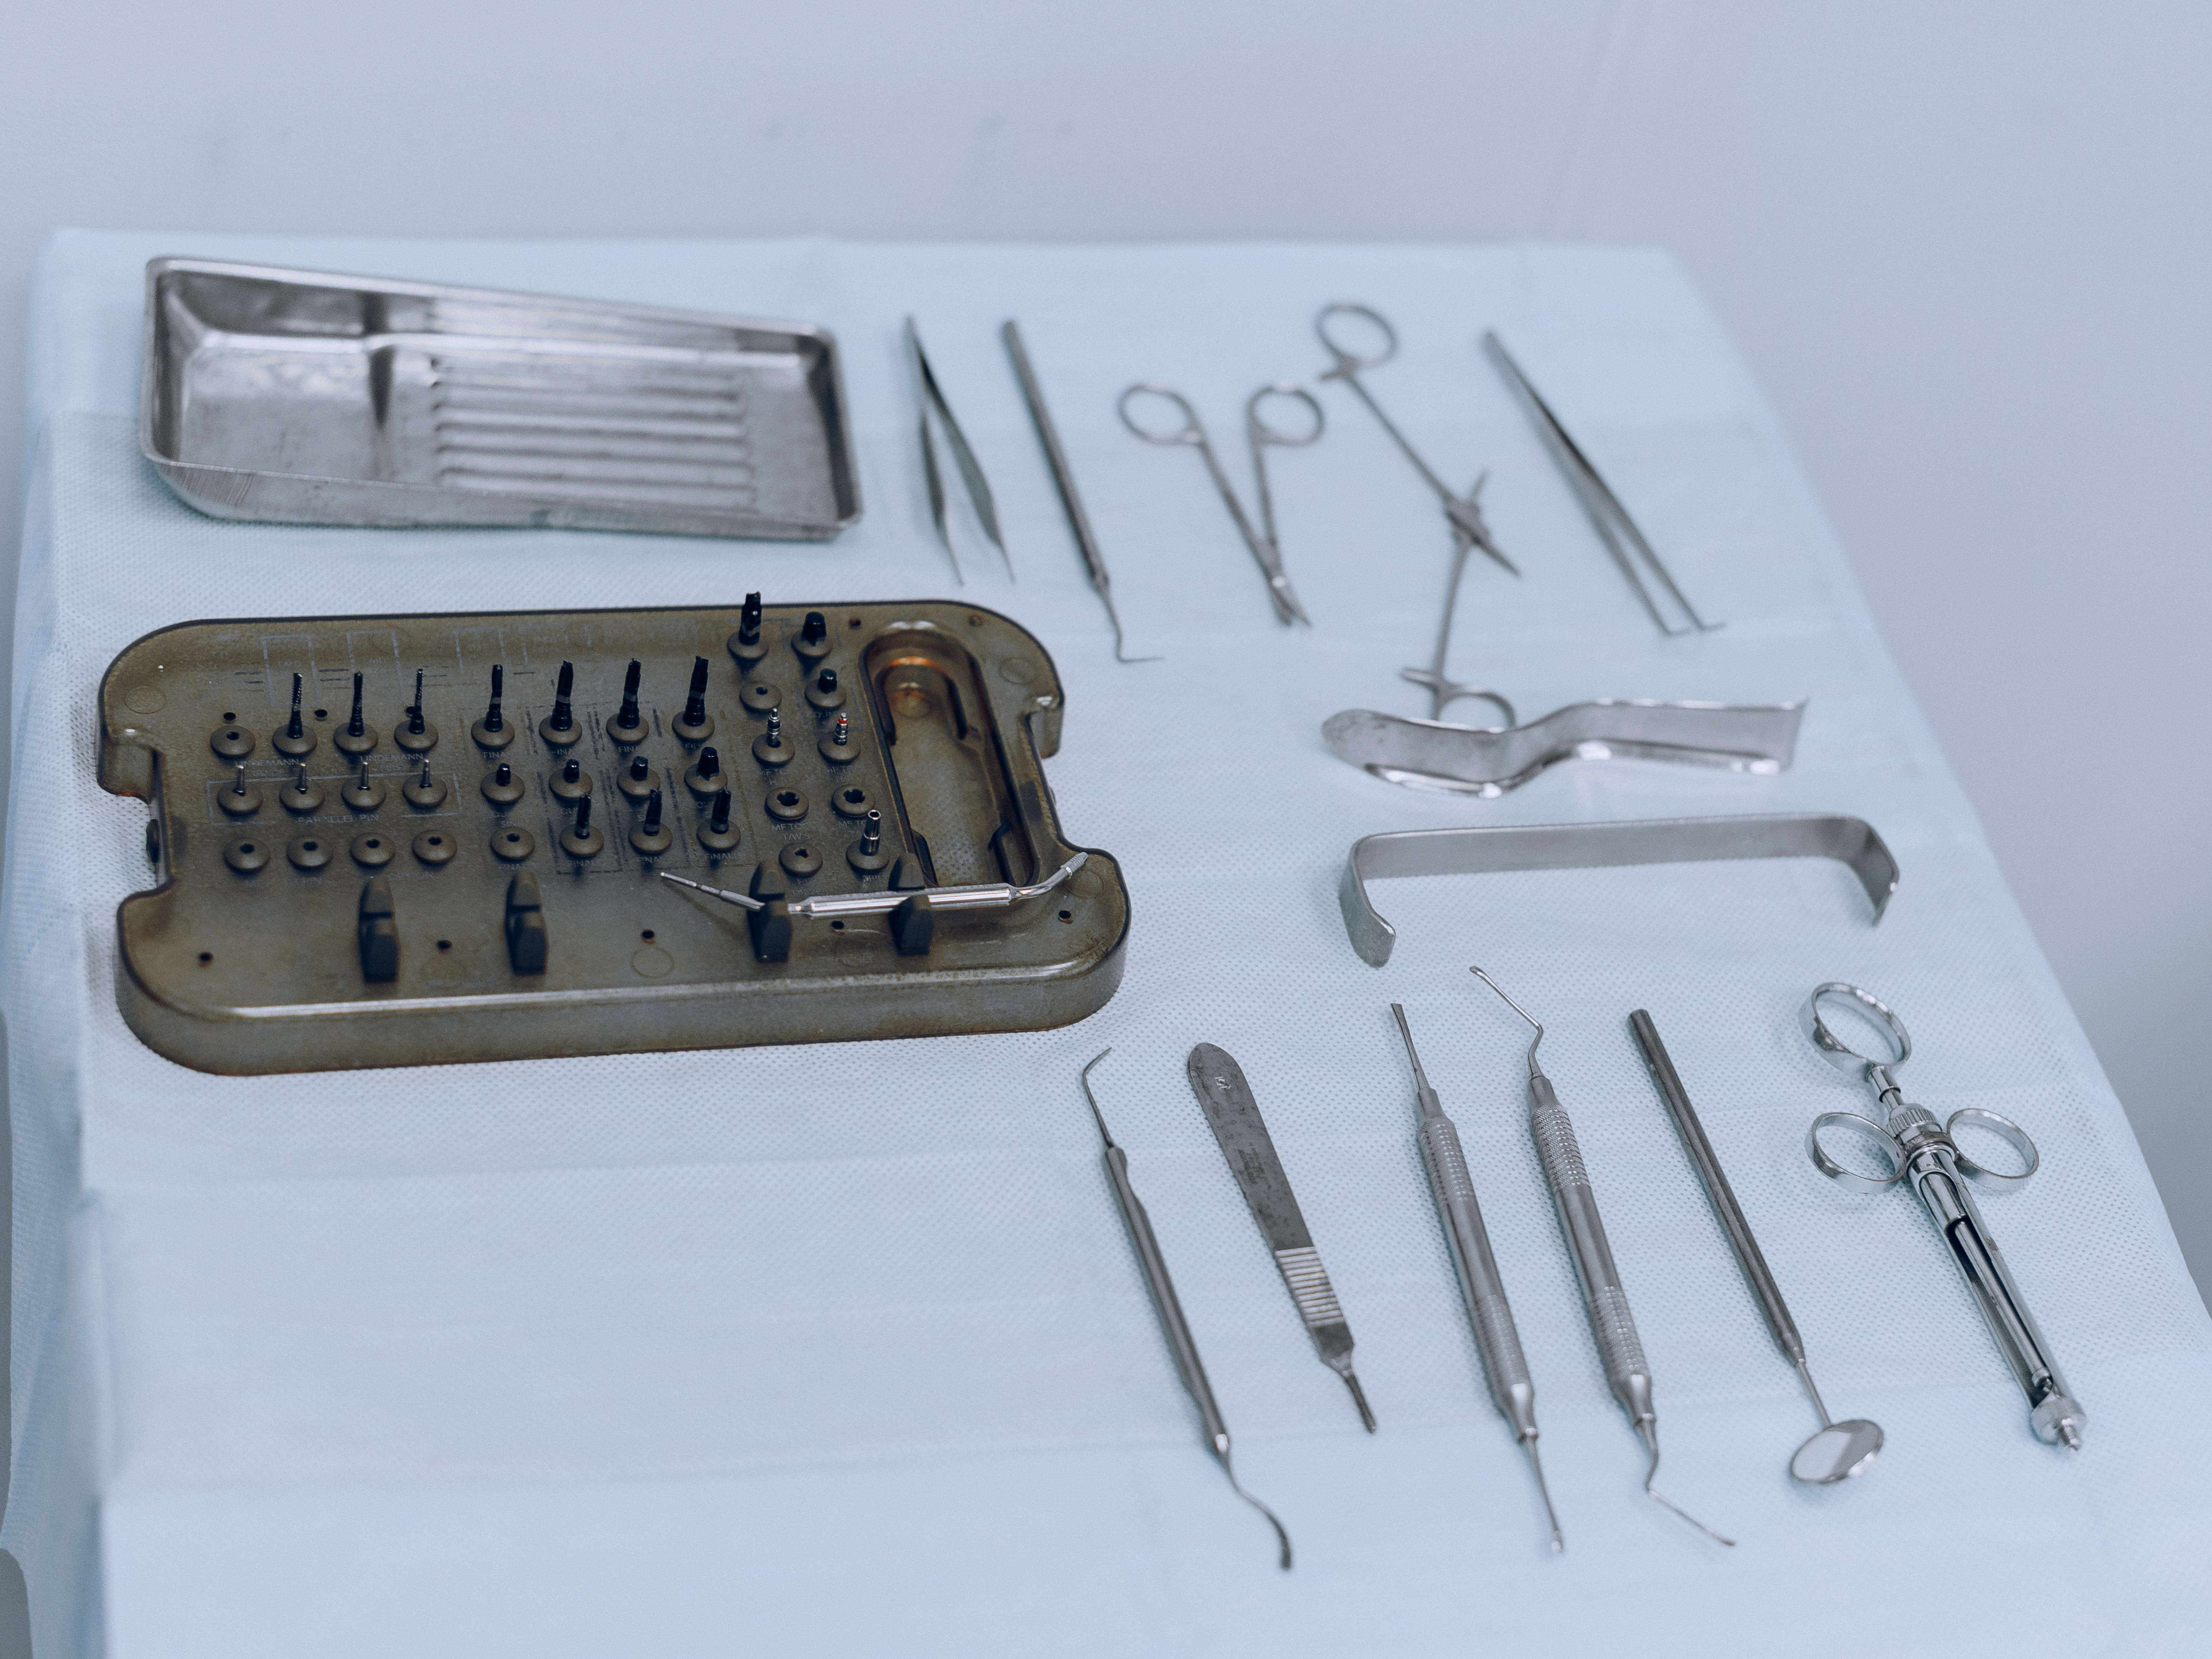

Современное оборудование

Технологии нового поколения и опытная команда — чтобы лечить не только эффективно, но и с комфортом для пациента.

Работаем на современном оборудовании KAVO.

Цифровая диагностика, 3D-оборудование и современные материалы помогают врачам точно диагностировать каждого пациента и действовать уверенно.

У нас всё продумано до мелочей — от первых снимков до результата, который возвращает здоровье, эстетику и уверенность в себе.

Работаем на современном оборудовании KAVO.

Цифровая диагностика, 3D-оборудование и современные материалы помогают врачам точно диагностировать каждого пациента и действовать уверенно.

У нас всё продумано до мелочей — от первых снимков до результата, который возвращает здоровье, эстетику и уверенность в себе.